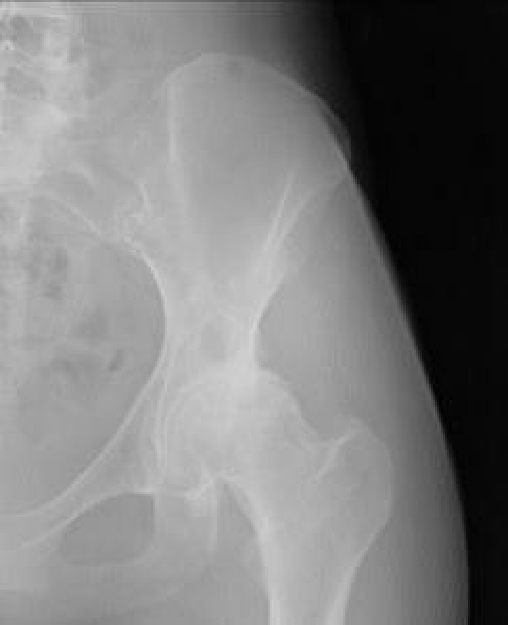

Dr Bose said, "You have end stage arthritis in your hip with early protrusio. However, your bone stock is very good. I am glad to report that you would be an excellent candidate for hip resurfacing surgery. However you must not delay for too long because of the protrusion (inward migration of the socket)."

And later in response to my question about whether dysplasia showed in the x-ray, Dr. Bose said, “You do have moderate dysplasia and there is no doubt that this is the reason as to why you have developed arthritis at this relatively young age. All young osteoarthritics will have some underlying problem like dysplasia, slipped epiphysis or femora-acetabular impingement. Your symptom level seems to be very high and certainly surgery would be justified in your case.”

Dr. De Smet said, "You are a candidate for resurfacing. You are not an easy case because you have some mismatch between size of femoral neck, femoral head and pelvis diameter for cup implant. Difficult but INDICATION for resurfacing! You start also to make destruction of the bone in the pelvis with a cyst, so maybe time to have something done."

Dr. McMinn’s assistant wrote, “Your x-ray pelvis shows DDH left hip and your DEXA scan showing bone density on this hip shows osteopenia. . . . It is possible you may need a dysplasia cup with supplementary screws and bone grafting.”